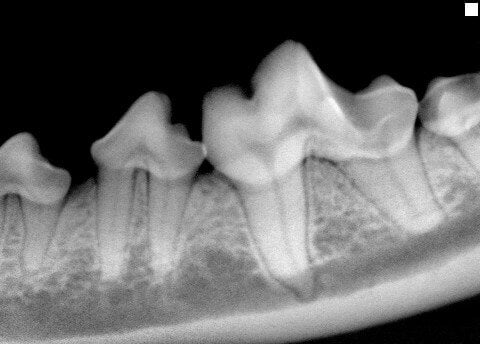

To remove this tartar, we will perform dental scaling, our most basic dental procedure. Our practice requires anesthesia for this. To ensure your pet's safety, we will first perform a full physical exam and then sometimes run blood tests. Inside the mouth, we utilize local anesthetic injections to reduce pain. We also have committed to excellence with digital dental radiography. This allows us to see every root tip and surrounding bone in your pet's mouth to make sure things are healthy under the gum line.

It is the goal of our practice for your pet to retain as many teeth as possible. However, sometimes surgical extraction of a severely diseased tooth is the only option to relieve pain or ensure that periodontal disease does not advance. If not extracted, many times a diseased tooth can compromise the surrounding tissue and neighboring teeth. If caught early, there are more treatment options available for periodontal disease.